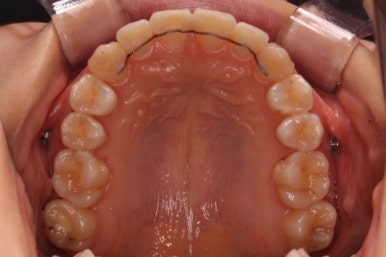

몇 달간의 마무리과정을 거치고 드디어 장치를 제거하였습니다.

위아래 앞니는 다시 틀어지지 말라고 유지철사를 붙였습니다.

위에는 탈착이 가능한 유지장치도 사용합니다. 2중으로 안전장치를 하는 것이죠.

치아는 매우 가지런해졌고, 과개교합도 개선이 되었으며 뻐드러진 앞니 각도도 정상적으로 회복이 되었습니다.